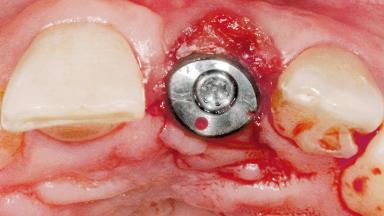

Late Flapless Placement of an Implant in a Maxillary Left Central Incisor Site

Type of Implants One-Piece

Attachment One-Piece

Bone Augmentation Horizontal|Staged

Soft Tissue Grafting Simultaneous